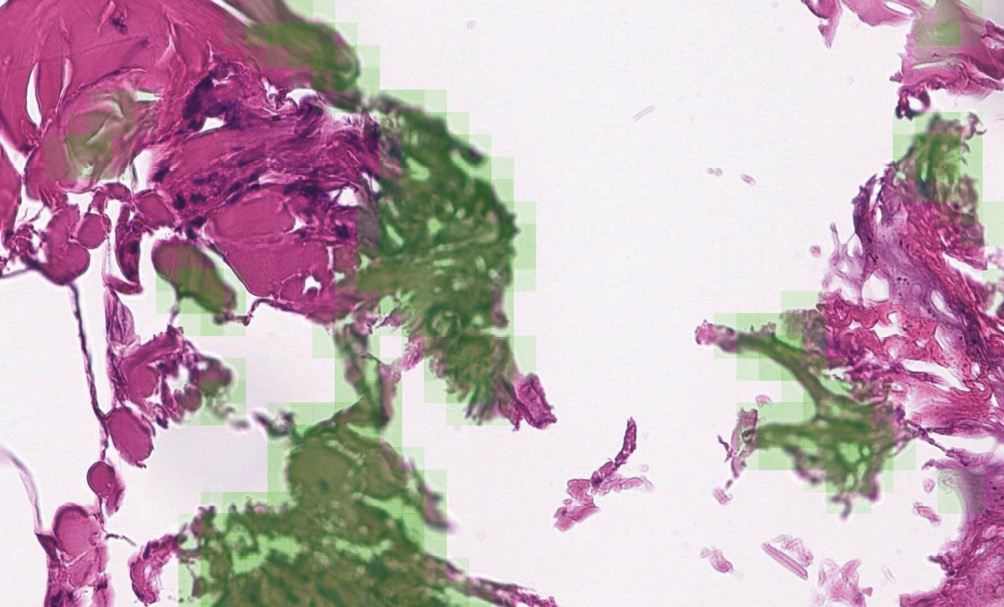

В табл. 1 и 2 продемонстрировано сравнение классического и предложенного нейросетевого метода на этих двух тестовых выборках. Для определения порогов классического метода использовался набор данных PATH-DT-MSU WSS2, изображения и размытия которого похожи на присутствующие в наборе WSS1. Соответственно нейросетевой метод, обученный, в том числе, на наборе данных, собранных классическим методом из WSS2, показывает на WSS1 немного более низкие результаты по сравнению с классическим методом. Однако классический метод [37] не способен строить карты размытия для целиком размытых изображений, отмечая все области карты размытия для таких изображений как четкие. Набор данных FocusPath состоит из целиком размытых и целиком четких изображений. В то же время нейросетевой метод лишен такого недостатка и демонстрирует удовлетворительные результаты на тестовой выборке из FocusPath. На рис. 7 зеленым отмечены результаты детекции реального размытия на изображении из набора данных WSS1.

Рис. 7. Визуализация детекций размытия